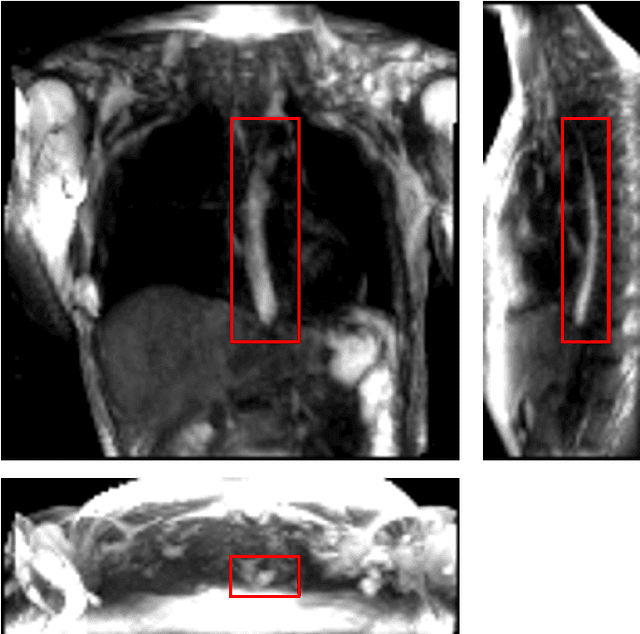

Abstract:Dynamic magnetic resonance imaging (MRI) is a popular medical imaging technique to generate image sequences of the flow of a contrast material inside tissues and organs. However, its application to imaging bolus movement through the esophagus has only been demonstrated in few feasibility studies and is relatively unexplored. In this work, we present a computational framework called mechanics-informed MRI (MRI-MECH) that enhances that capability thereby increasing the applicability of dynamic MRI for diagnosing esophageal disorders. Pineapple juice was used as the swallowed contrast material for the dynamic MRI and the MRI image sequence was used as input to the MRI-MECH. The MRI-MECH modeled the esophagus as a flexible one-dimensional tube and the elastic tube walls followed a linear tube law. Flow through the esophagus was then governed by one-dimensional mass and momentum conservation equations. These equations were solved using a physics-informed neural network (PINN). The PINN minimized the difference between the measurements from the MRI and model predictions ensuring that the physics of the fluid flow problem was always followed. MRI-MECH calculated the fluid velocity and pressure during esophageal transit and estimated the mechanical health of the esophagus by calculating wall stiffness and active relaxation. Additionally, MRI-MECH predicted missing information about the lower esophageal sphincter during the emptying process, demonstrating its applicability to scenarios with missing data or poor image resolution. In addition to potentially improving clinical decisions based on quantitative estimates of the mechanical health of the esophagus, MRI-MECH can also be enhanced for application to other medical imaging modalities to enhance their functionality as well.